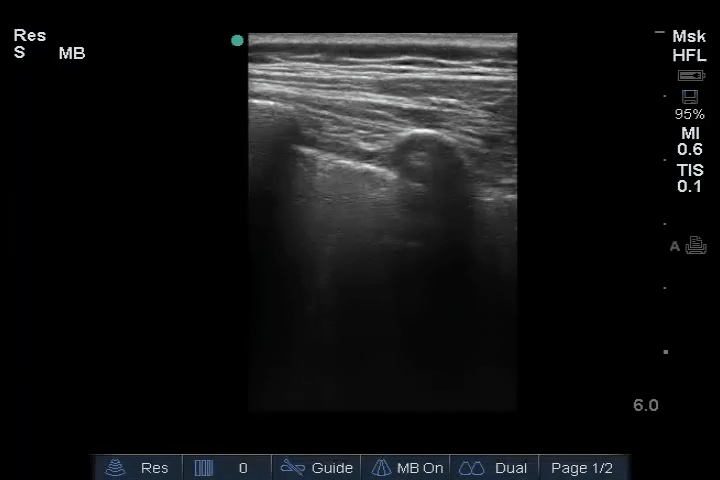

02_Lung_Ant_Left – B-lines